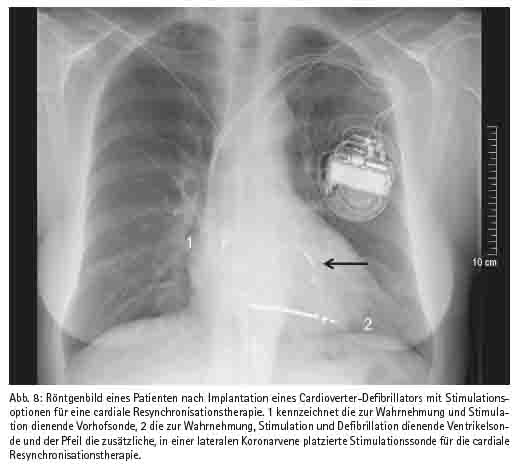

Hier sind an neueren Methoden die chirurgische Ablation bei Patienten mit Vorhofflimmern, die Implantation von diagnostischen Systemen sowie die Implantation von Systemen zu cardialen Resynchronisations-Therapie (CRT) zu erwähnen (Abb. 8). Die Ablation von Vorhofflimmern hat eine hohe Erfolgsquote, d. h. bei einem hohen Prozentsatz der Patienten bleibt postoperativ der Sinusrhythmus sowie die Transportfunktion des Vorhofs dauerhaft erhalten. Diese Methode wird überwiegend interventionell durchgeführt, kommt aber auch als Zusatzschritt bei herzchirurgischen Eingriffen zur Anwendung, wobei neben der Ablation in der Regel auch der chirurgische Verschluss des linken Herzohrs mit Excision dieser Struktur vorgenommen wird, um die Thromboemboliegefahr zu minimieren. Diagnostische Implantate werden von uns wie von anderen bei Patienten eingesetzt, deren Rhythmusstörungen mit den ansonsten üblichen Mitteln nicht diagnostiziert werden können. Damit konkurriert dies Verfahren mit anderen Methoden, so dass es trotz hoher Diagnosesicherheit bislang (zu) wenig eingesetzt wird. Demgegenüber haben die CRT-Geräte seit ihrer Einführung rasch an Attraktivität gewonnen, da damit bei einer nennenswerten Zahl von Patienten eine teilweise dramatische Verbesserung der Herzinsuffizienz-Symptome erreicht wird. Wir haben 2001 das erste CRT System im nördlichen Rheinland-Pfalz implantiert und seitdem diese Therapieform bei über 150 Patienten zum Einsatz gebracht. Schließlich gilt die Herz- und Gefäßchirurgie des BwZKrhs als Zentrum für die chirurgische Behandlung von Komplikationen bei extern therapierten Patienten mit kardialen Rhythmusimplantaten. Da diese Komplikationen in einer Häufigkeit von über 10 % auftreten, wird in der Zukunft auch an dieser Form von Operationen kein Mangel sein.